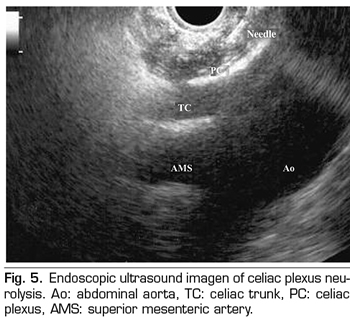

ENDOSCOPIC ULTRASOUND NEUROLYSIS OF THE CELIAC PLEXUS

Endoscopic ultrasound offers the advantage of larger visualization of the celiac plexus at a short proximity, allowing larger precision and safety in the administration of the neurolytic agent and avoiding injection into vascular structures through the use of Doppler (37) (Figure 5). However, the studies supporting endoscopic ultrasound neurolysis, considered similarly to percutaneous technique as a rescue therapy, are limited to retrospective uncontrolled studies (38). Pauli et al. published a meta-analysis that concludes that this technique achieves an 80% pain reduction in patients with pancreatic cancer (39). Some studies show a slight decrease in opioid consumption, but without strong scientific evidence.